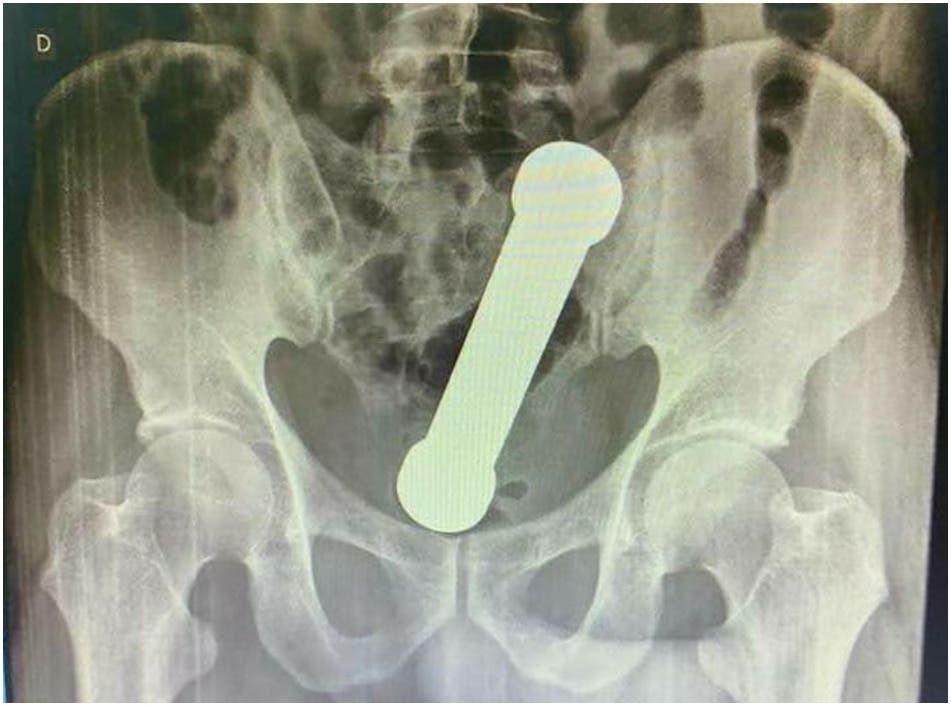

Las radiografías abdominales revelaron que el hombre tenía una mancuerna de 20 centímetros atorada a la altura del lugar en que el colon se conecta con el recto.

De acuerdo a lo confesado por el sujeto, dos días atrás se había introducido la pesa metálica de dos kilos por motivos sexuales. Lamentablemente, después no pudo extraer el objeto de su interior.